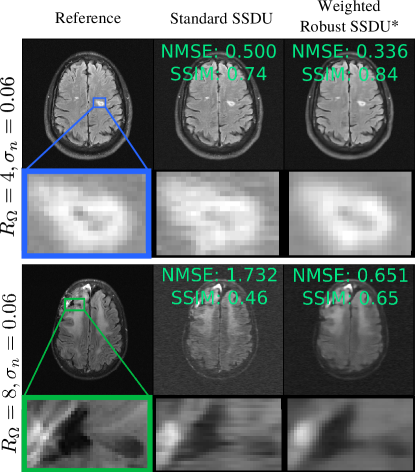

Figure 9: Clinical regions of interest annotated via fastMRI+ [36] at σn=0.06subscript𝜎𝑛0.06\sigma_{n}=0.06. The top image shows a lacunar infarct and the bottom shows a resection cavity. The proposed method Weighted Robust SSDU has improved sharpness compared to Standard SSDU, which has substantial reconstruction errors arising from the measurement noise.

Fig. 8 shows the test set loss for the methods designed for sub-sampled, noisy training data. The weighted and unweighted variants of the proposed Robust SSDU performed within 0.17dB of the best-case benchmark, despite only having access to noisy, sub-sampled training data. Noise2Recon-SS performs well in some cases, particularly at RΩ=4subscript𝑅Ω4R_{\Omega}=4, but is consistently outperformed by both variants of Robust SSDU. Fig. 7 shows example reconstructions, demonstrating similar performance to the best-case benchmark qualitatively. Fig. 9 compares Standard SSDU and Weighted Robust SSDU using clinical expert bounding boxes from fastMRI+ [36], which shows that the proposed method has substantially enhanced pathology visualization.

The examples in figures 5, 7 and 9 show that proposed methods are qualitatively very similar to the best-case benchmark, and substantially improve over methods without denoising, whose reconstructions are visibly corrupted with measurement noise. The examples exhibit some loss of detail and blurring at tissue boundaries, especially at RΩ=8subscript𝑅Ω8R_{\Omega}=8. However, the extent of detail loss is similar in the benchmark, indicating that the loss of detail is not a limitation of the proposed methods. Rather, the qualitative performance is limited by the other factors such as the architecture, dataset and choice of loss function. This can also be explained in part by noting that the high-frequency regions of k-space, which provide fine details, typically have smaller signal so are particularly challenging to recover in the presence of significant measurement noise.